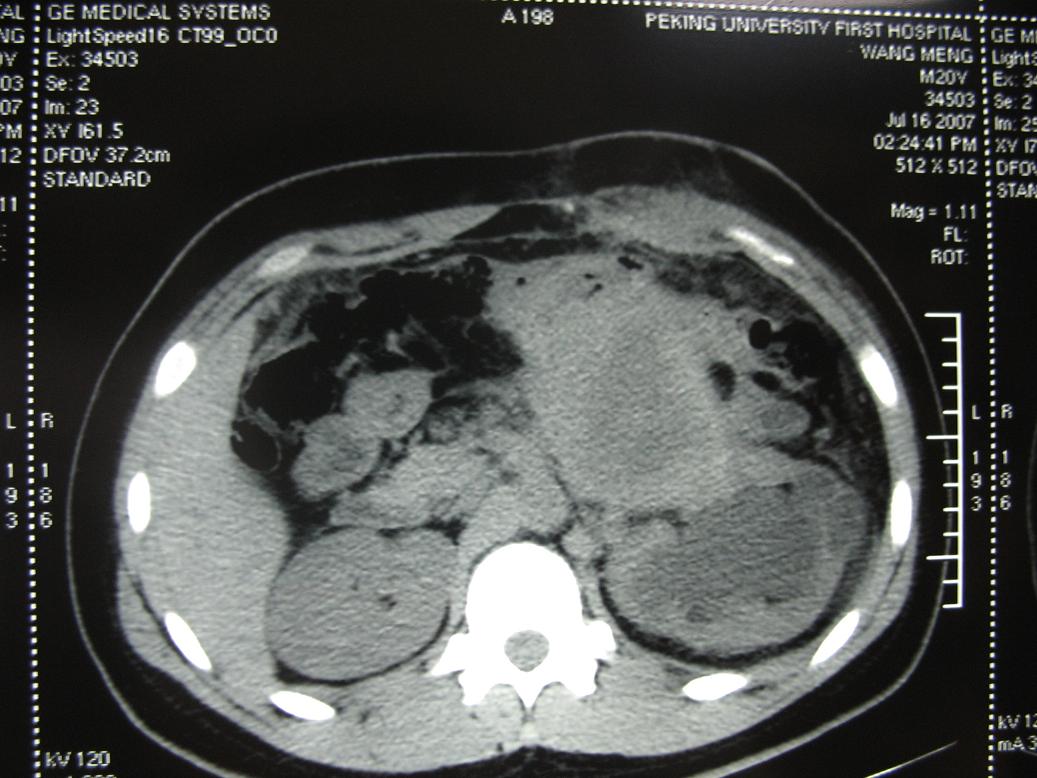

m20,发现腹部肿物二月.

1、m20,发现腹部肿物二月。

2、左侧腹膜后囊实性占位性病变,有完整包膜,周围脏器及血管呈受压移位改变,左肾积水,肾实质变薄,增强扫描示病变包膜有强化,因图片太少,实性部分是否强化不好判断。

3、诊断:结合病人年龄,左肾改变考肿虑为输尿管受压肾积水时间长,左肾实质萎缩,病变未见明显外侵征象,本人首先考虑为神经源性瘤囊变可能性大。